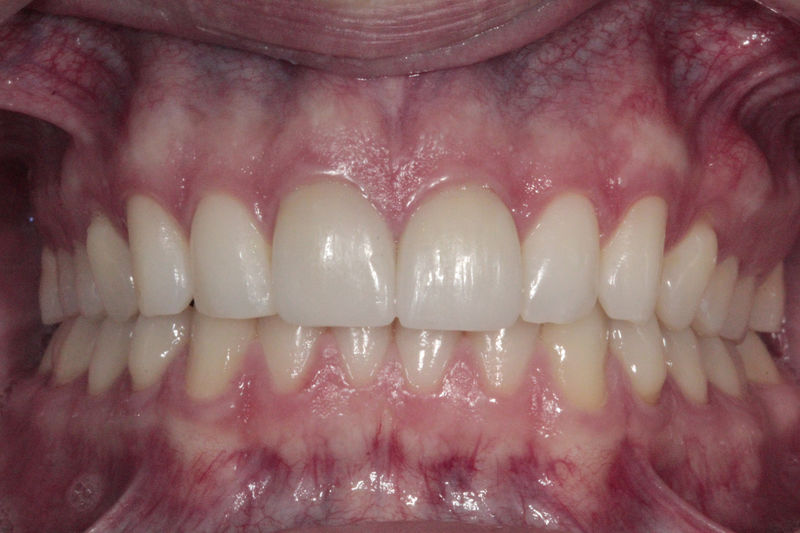

Ortodoncia y coronas.